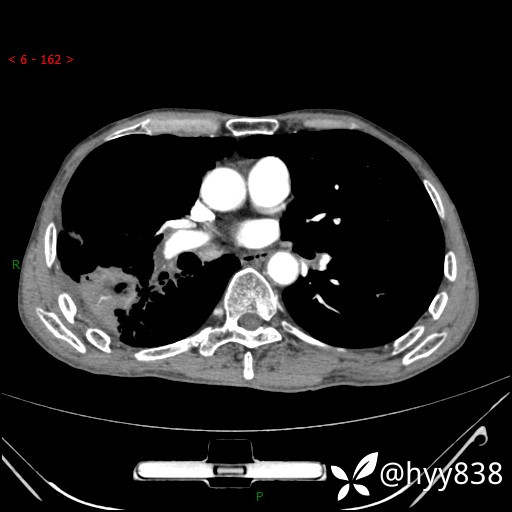

静脉期